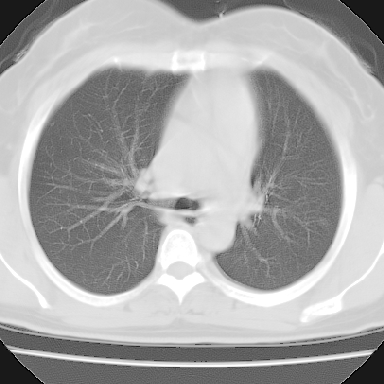

左下肺肿块影,内可以见小泡征,并见厚壁空洞形成,洞内缘可见壁结节。靠近胸膜侧可见胸膜肥厚粘连。双肺可见多发性小结节影。

考虑:左下空洞性肺癌伴两肺转移

偏心性厚壁空洞,壁结节,胸膜肥厚粘连,双肺多发性小结节灶。这么多典型征象,即使错了也错的有道理!

左下肺有空洞,壁厚薄不均,壁结节,两肺多发小结节影,腋窝下可疑淋巴结肿大,综上所述考虑周围性肺癌并两肺转移可能性大,建议穿刺活检。

支持癌性空洞:壁厚,无液平,内壁不规则,外壁呈分叶状,较大,偏心性,壁结节,胸膜凹陷,转移灶。